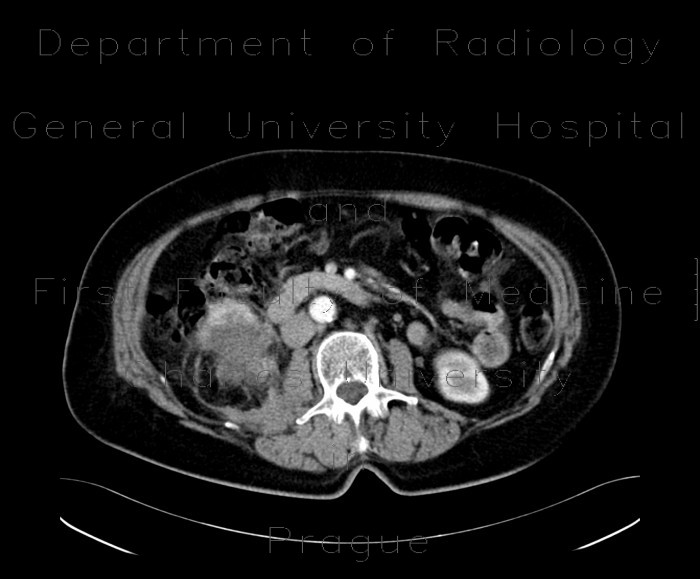

Embolization Renal Cell Carcinoma

Renal cell carcinoma Renal cell carcinoma (RCC), also known as renal cell cancer or renal cell adenocarcinoma , is by far the most common type of kidney cancer. ... Get Doc

Interventional Radiology Treatments for Kidney Cancer Management of Advanced Renal Cell Carcinoma Arterial Embolization Advanced renal cell carcinoma tumors are often quite large and invade adjacent structures and veins. ... Document Viewer